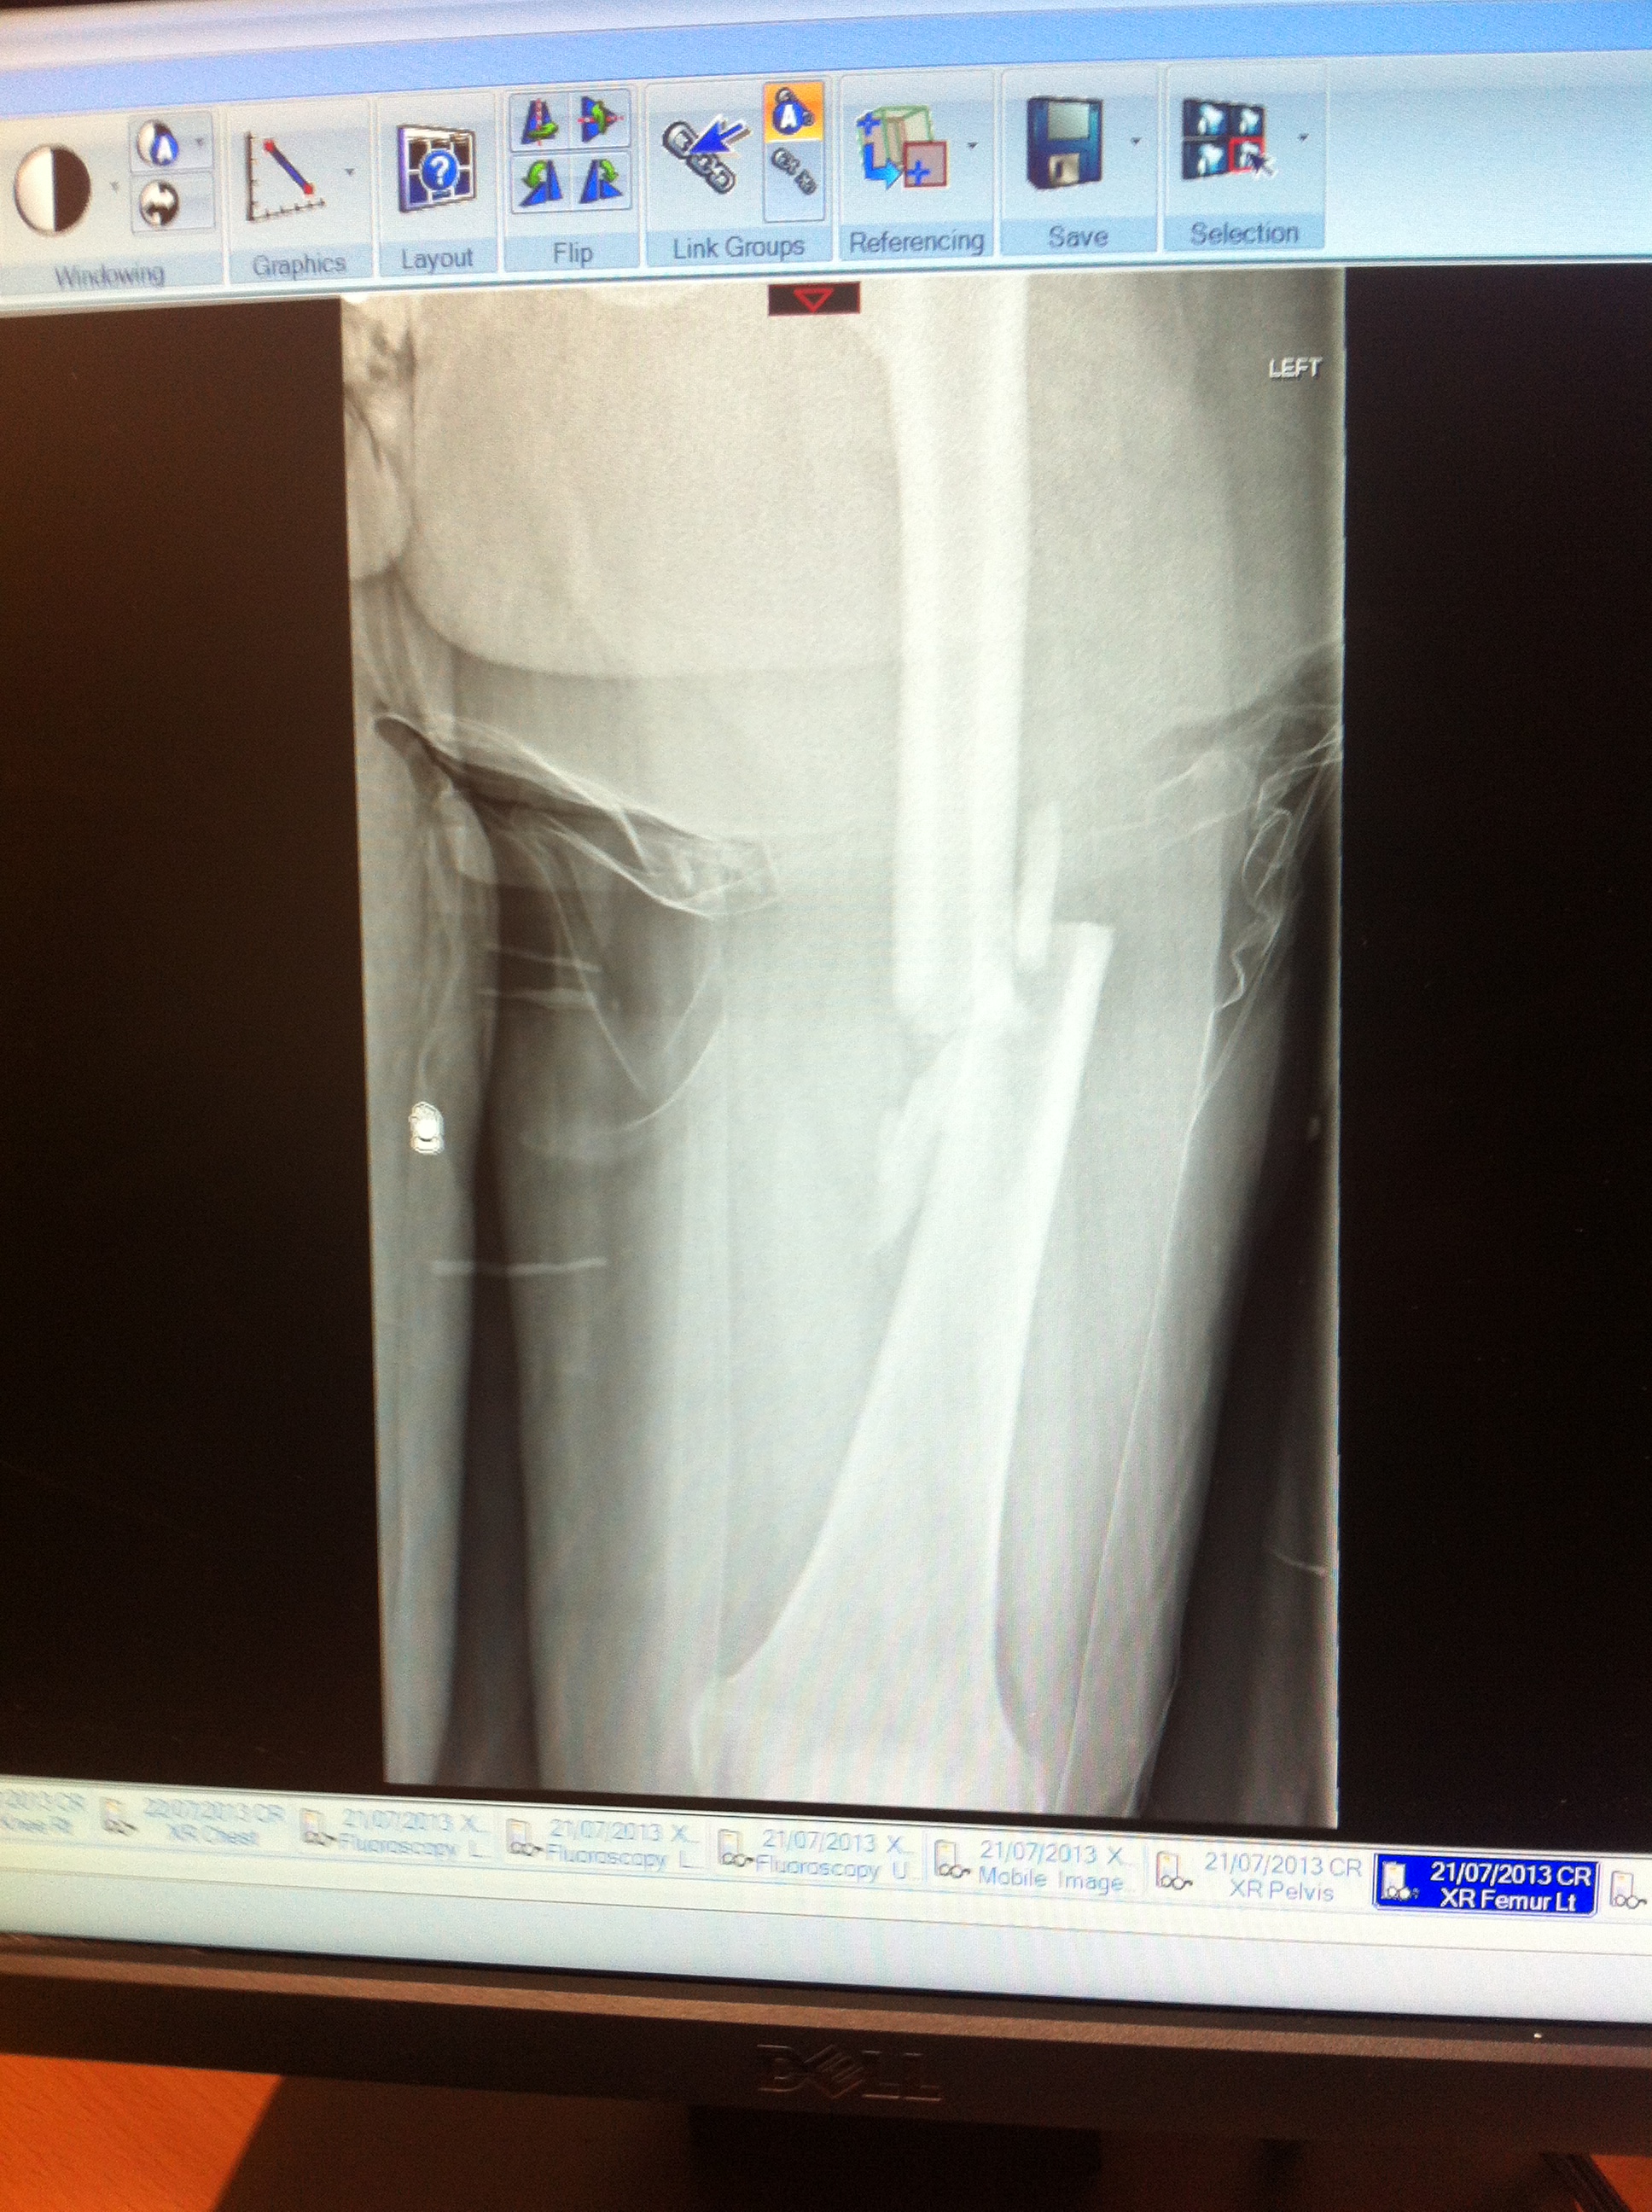

Femur (no wonder I hadn’t been able to move my leg at the crash site….)

Pretty impressive collection of fractures – never bothered seeing the rib ones. Ok, 10 of them were smashed, but I figure that I’m not going to see that much that clearly.

Finally seeing the original x -rays has made me realise how bad my fractures actually were. It still sounds bonkers when I say it, but, in my head, I wasn’t that poorly.